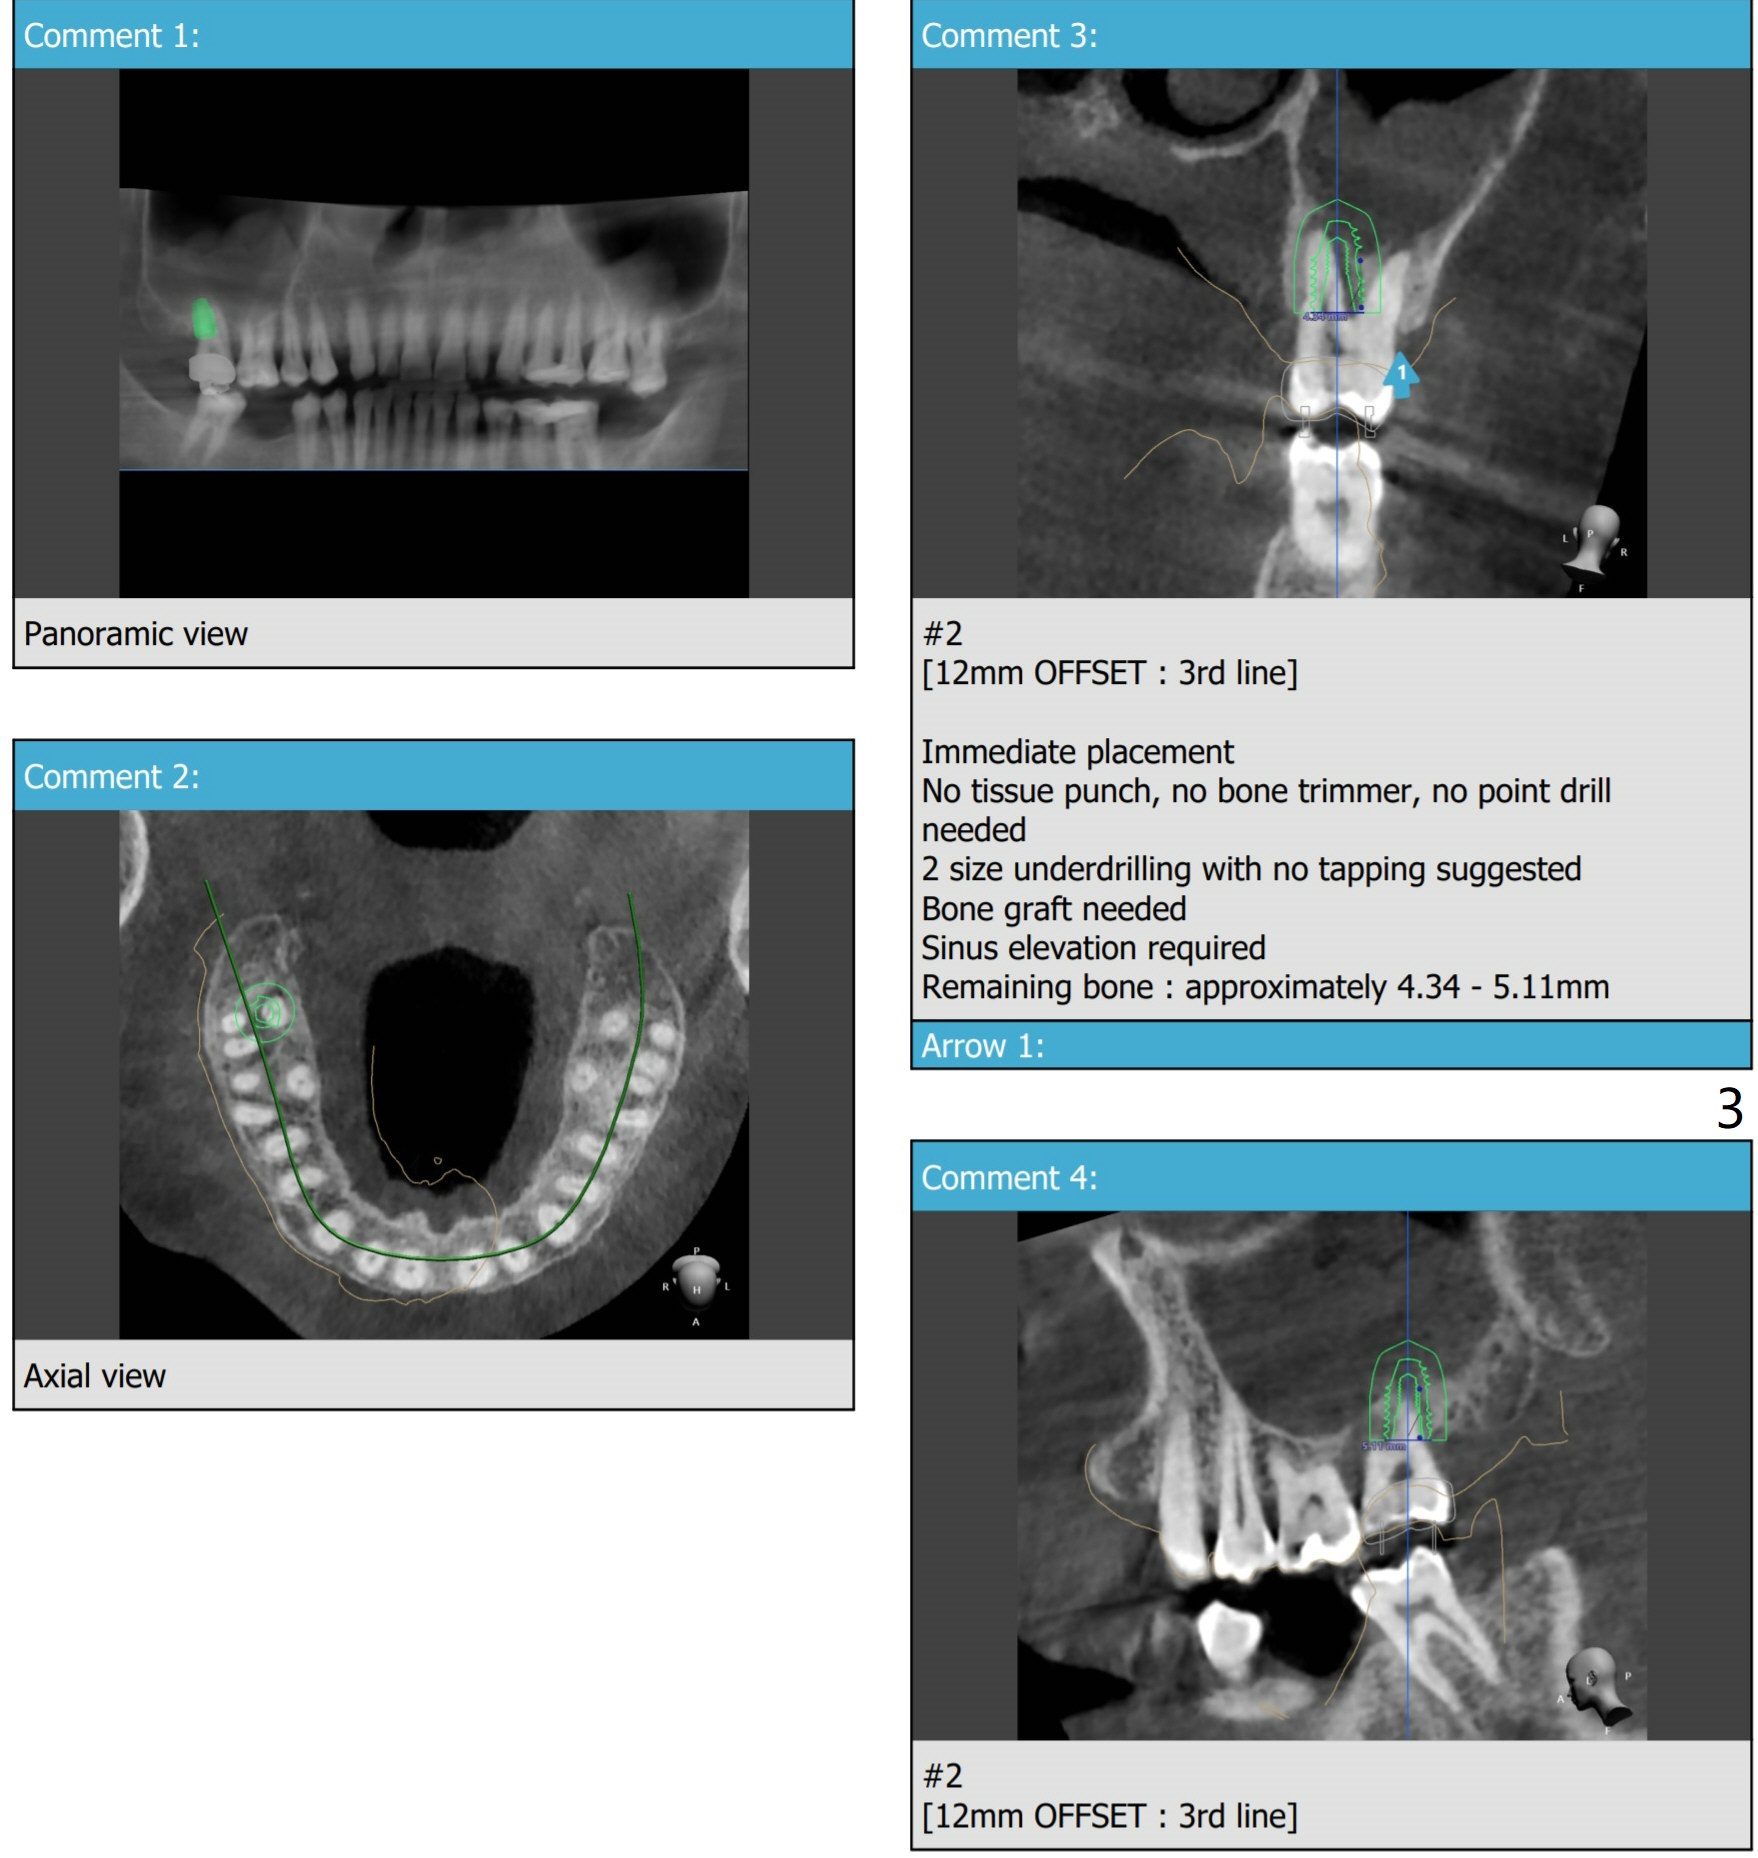

Implant Placed in Palatal Socket

Implant length changes to 10 mm. Place 5x9 mm IBS one. Use 4 and 4.5x10 mm IS dummy ones for sinus lift. Sinus Approach Kit and Treatment Planning one.